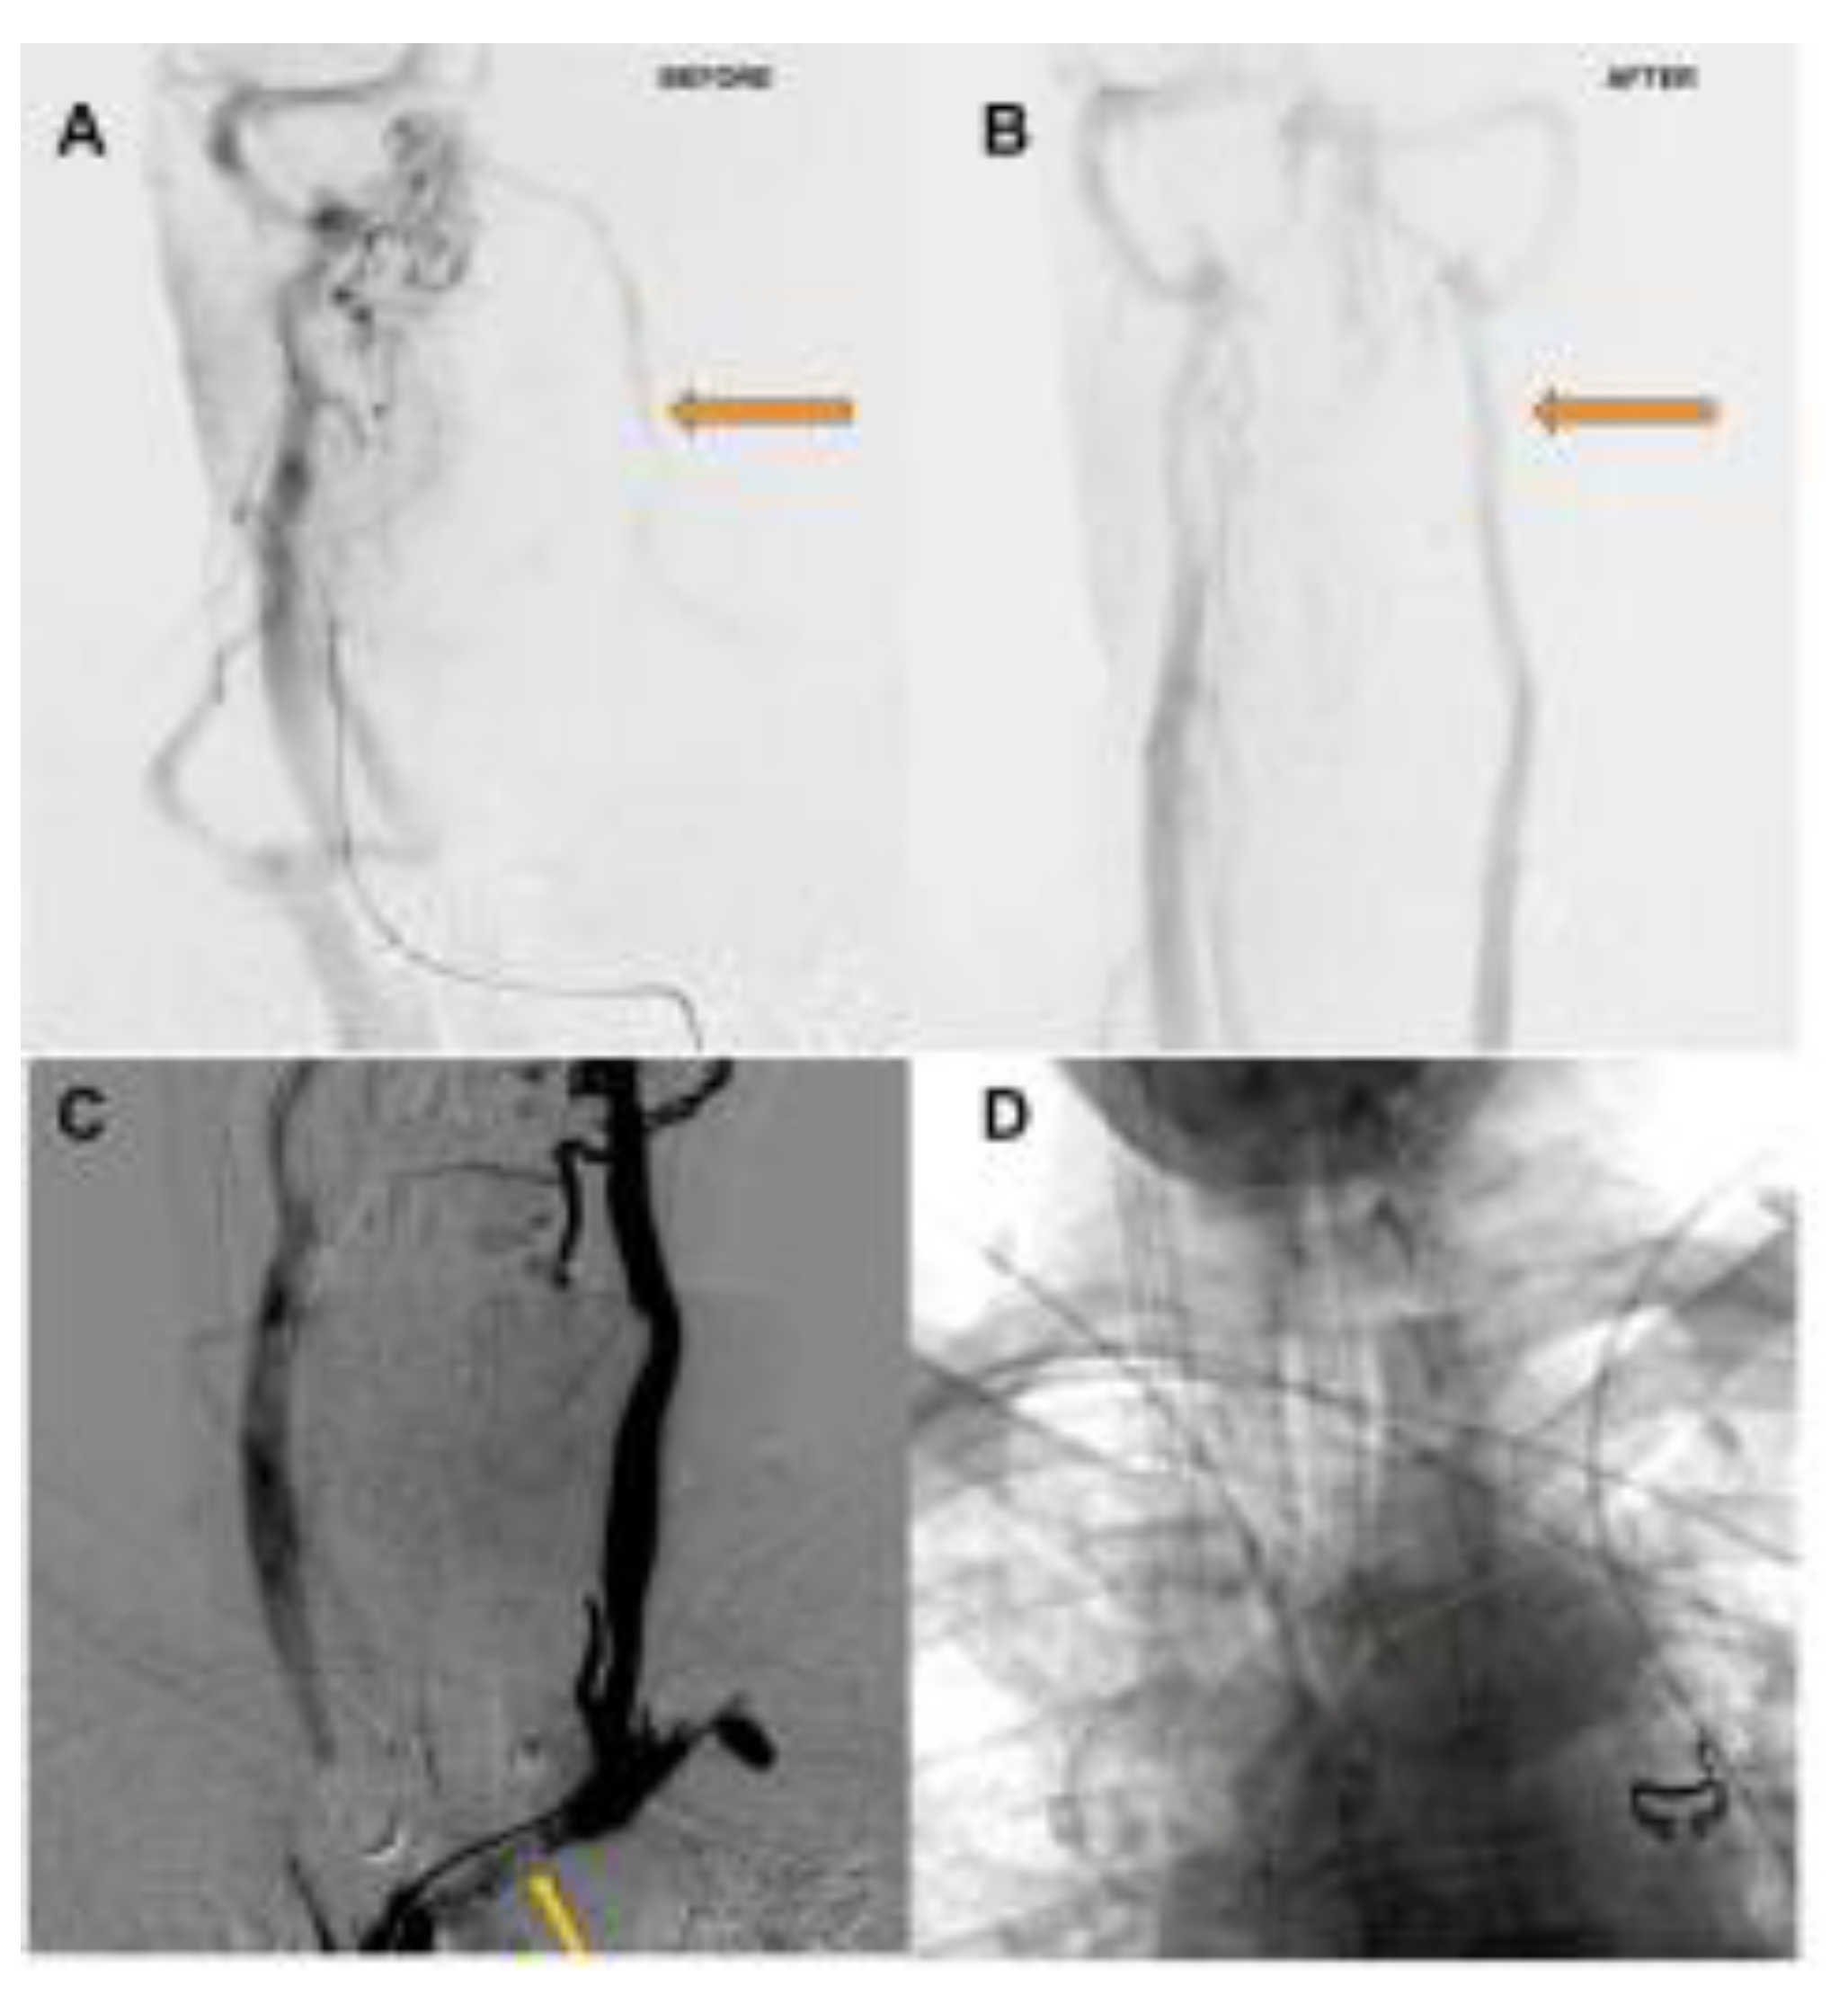

Preprints 78109 g001

The clinical hallmarks of this condition include headaches, often chronic, exacerbated by exertion or valsalva and frequently refractory to standard medical treatment, vertigo/dysequilibrium, and tinnitus/ hearing impairment. Some patients report a disabling "brain fog" in addition. Conventional catheter-based angiography is useful in depicting the delay in venous emptying or stagnation or slowing of flow in the left internal jugular vein. It is also useful in depicting a radiological improvement in flow after treatment. Conventional catheter-based venography is a poor modality to detect this condition, as the plane of compression is usually parallel to the antero-posterior plane and the lateral plane is obscured by the patient's arms. Venous stagnation, reflux and diverticula are often noted.

Figure 2. A. Delayed phase of arterial angiogram showing poor flow in the left internal jugular vein (orange arrow) with B. normalization after stenting of the left brachiocephalic vein C. Left Internal Jugular Vein injection with retrograde flow into the cranium, continuing across the torcula and emptying via the right internal jugular vein due to LBV compression (orange arrow) D. Left Brachiocephalic Stent Outlined with orange line.

As an interesting aside, there occurs an intersection between pacemakers / defibrillators and LBV compression. The leads are typically inserted on the side of the non-dominant hand [12]. They can occupy some valuable space in the LBV and produce the above symptoms.

Figure 3. Pacemaker leads compounding the venous outflow obstruction in the setting of LBV compression.